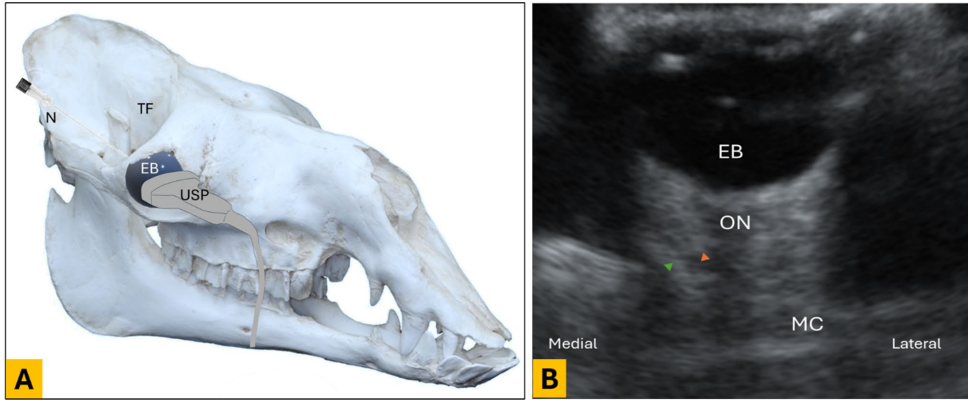

超声成像发现

通过眶上窝入路,研究者清晰观察到肌肉锥体(Muscle cone, MC)的强回声结构(直径6.2±0.8 cm)。